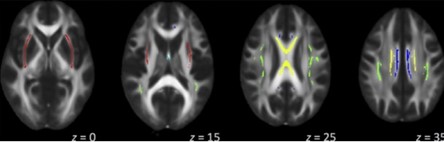

A propósito de lo anterior, una investigación realizó un análisis sistemático sobre estudios de tomografía por emisión de positrones (TEP) y resonancia magnética funcional (RMf) centradas en la CPF en relación con adicciones. Se incluyó la corteza orbitofrontal (COF), la corteza cingulada anterior (CAA) y la corteza prefrontal dorsolateral (CPFDL).(7)

En este estudio que se viene comentando, las áreas de la CPF muestran diferencias actividades entre individuos con adicción y casos controles saludables durante tareas que involucran atención y memoria de trabajo (verde), toma de decisiones (azul claro), control inhibitorio (amarillo), emoción y motivación (rojo) y la reactividad de la señal y la administración del fármaco (naranja). Además, en algunas áreas de la CPF, la actividad se correlaciona con el desempeño de la tarea o el uso de drogas (azul oscuro)(7) (ver Imagen 4-a).

De igual forma, en este mismo estudio se evidenciaron cambios en la actividad cerebral relacionados con las características clínicas de la adicción, incluida la intoxicación y los atracones (rojo, considerando que las drogas se usaron dentro de las 48 horas posteriores al estudio), la ansiedad (rosa, las drogas se usaron una o dos semanas antes del estudio) y la abstinencia (púrpura, los medicamentos se usaron más de tres semanas antes del estudio(7) (ver Imagen 4-b).